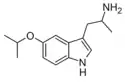

α-Alkyltryptamines are a group of substituted tryptamines which possess an alkyl group, such as a methyl or ethyl group, attached at the alpha carbon, and in most cases no substitution on the amine nitrogen.[17][18][19] α-Alkylation of tryptamine makes it much more metabolically stable and resistant to degradation by monoamine oxidase, resulting in increased potency and greatly lengthened half-life.[19] This is analogous to α-methylation of phenethylamine into amphetamine.[19]

Many α-alkyltryptamines are drugs, acting as monoamine releasing agents, non-selective serotonin receptor agonists, and/or monoamine oxidase inhibitors,[20][21][22][23] and produce psychostimulant, entactogen, and/or psychedelic effects.[17][18][19] The most well-known of these agents are α-methyltryptamine (αMT) and α-ethyltryptamine (αET), both of which were used clinically as antidepressants for a brief period of time in the past and are abused as recreational drugs.[18][19] In accordance with its action as a dual releasing agent of serotonin and dopamine, αET has been found to produce serotonergic neurotoxicity similarly to amphetamines like MDMA and PCA, and the same is also likely to hold true for other serotonin and dopamine-releasing α-alkyltryptamines such as αMT, 5-MeO-αMT, and various others.[24]

5-Isopropoxy-αMT | 1-{5-[(propan-2-yl)oxy]-1H-indol-3-yl}propan-2-amine | |

BW-723C86 | 1-[5-(2-Thienylmethoxy)-1H-indol-3-yl]-2-propanamine | 160521-72-2 |